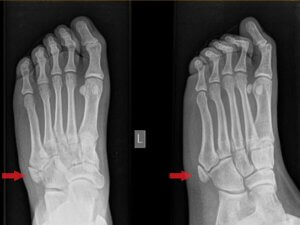

تمامی افرادی که علائم شکستگی استخوان متاتارسال پنجم را تجربه می کنند باید هر چه سریع تر جهت دریافت تشخیص و درمان مناسب به جراح ارتوپد مراجعه نمایند. جراح جهت تشخیص مناسب مشکل نحوه بروز آسیب یا زمان شروع درد را از بیمار سوال می کند. پزشک با فشار دادن آرام بر نواحی مختلف پای مبتلا را معاینه، محل درد را مشخص و انجام تصویر برداری اشعه ایکس را تجویز می کند.

از آن جایی که شکستگی جونز گاهی اوقات در تصویر برداری های اولیه مشخص نمی شود امکان دارد دیگر آزمایش های تصویر برداری نیز برای فرد تجویز شوند. شکستگی جونز معمولا در تصاویر اشعه ایکس پای آسیب دیده نمایان است. در صورت عدم مشاهده شکستگی در تصویر برداری با اشعه ایکس، تصویر برداری با امواج مغناطیسی (MRI) مفید خواهد بود. آزمایش سی تی اسکن برای سنجش التیام شکستگی ها به کار گرفته می شود.